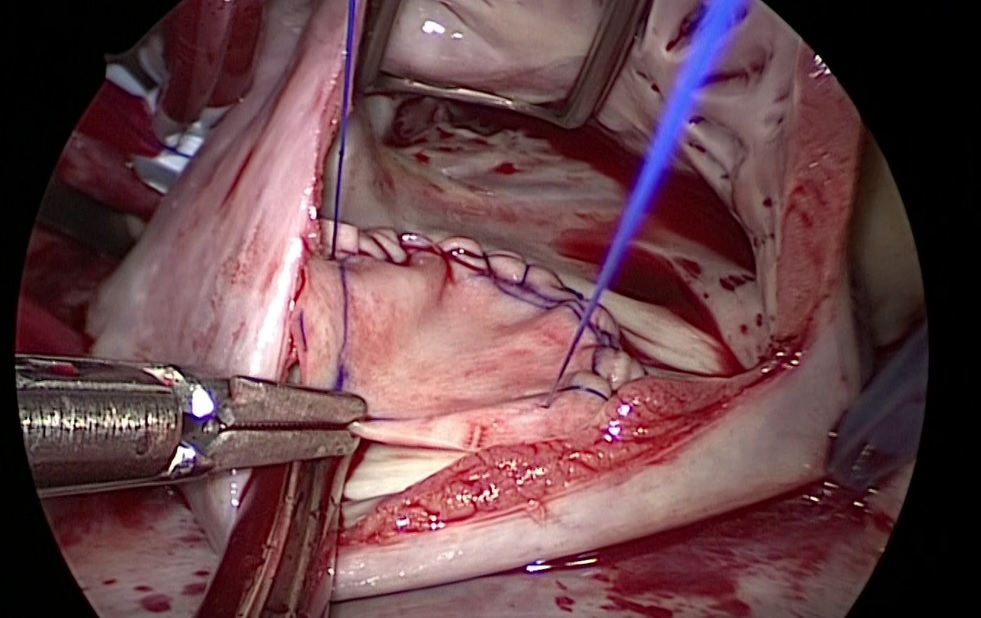

これが上から見た実際の距離です。従来の内視鏡で距離がわかりにくかったもう一つの大きな理由は立体視出来なかった事もあります。3D内視鏡はこの点で有利で、もはや直視で僧帽弁MICSをする理由は無くなったと感じます。

これが上から見た実際の距離です。従来の内視鏡で距離がわかりにくかったもう一つの大きな理由は立体視出来なかった事もあります。3D内視鏡はこの点で有利で、もはや直視で僧帽弁MICSをする理由は無くなったと感じます。 エチコンさん主催の弓部置換のウェットラボのお手伝いをしました。荻野先生がコースディレクターです。ラボのセッティングは事前にエチコンさんと打ち合わせして、箱の底に下行大動脈を固定するようにしたところ割と本物ぽい雰囲気になりました。動脈瘤手術はどんどんステントグラフトに押されて減ってますが、ステントで治るなら患者さんにとっては良い事です。日赤もステント治療は数年前まで正直全国レベルから遅れを取っていました。3年前から自転車仲間の坂口(兄)先生に指導して頂き、澤木医師がステント実施医指導医を取り今では県内有数の治療実績となり弱点を克服出来ました。